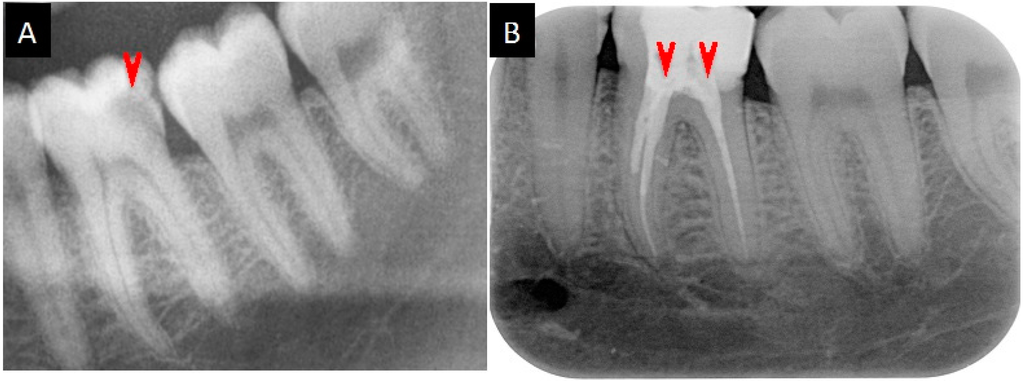

2.5. Medication Reports